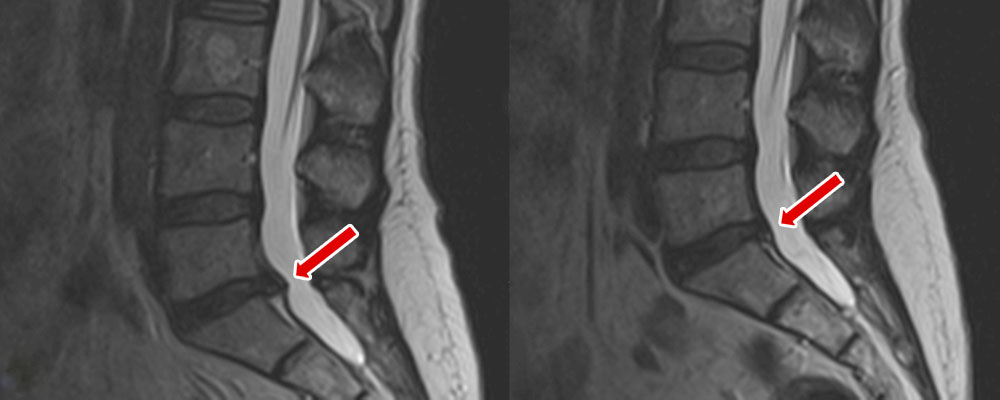

Bandscheibenvorfall vor und nach der Behandlung mit GammaSwing / SwingMed

Die Behandlung mit GammaSwing / SwingMed bewirkt eine sanfte Dehnung der Muskeln und Bänder, führt zu einer schonenden Separation der Gelenksflächen der kleinen Wirbelgelenke sowie zu einer Druckverminderung (Unterdruck) im Bereich der Bandscheiben. Gerade durch die Einflussnahme auf die Bandscheibe wird deren Regeneration (Zufuhr von Nährstoffen seitens der Wirbelkörper mittels Diffusion) unterstützt, ebenso kann es zur Rückbildung von Vorwölbungen und Vorfällen der Bandscheiben kommen.

Nach den zahlreichen, bisher durchgeführten Behandlungen stellt die Therapie mit einem dynamischen Extensionsgerät eine hilfreiche medizinische Innovation und Bereicherung des therapeutischen Spektrums für die Behandlung von Erkrankungen der Wirbelsäule und mitunter sogar eine Alternative zur Bandscheiben-Operation dar.